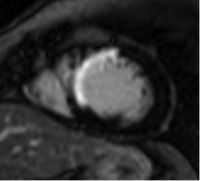

(心臓サルコイドーシス)前壁~中隔外膜側に遅延造影像を認め、原疾患により障害を受けて線維化した心筋を認めます。